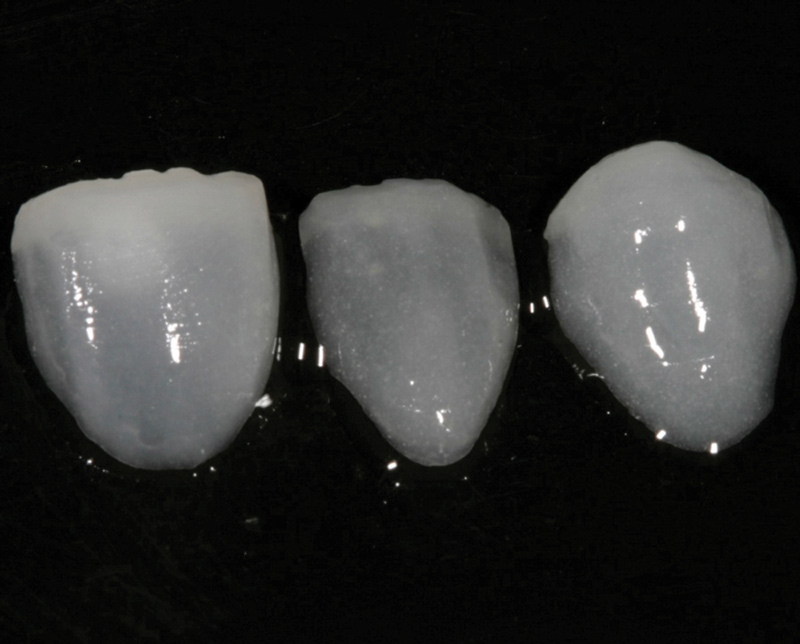

Fig 1. Preoperative (Fig 1), preparation (Fig 2), and final (Fig 3) postoperative images of a two-unit CL-I feldspathic veneer case.

Figure 1

Class I (CL-I) powder and liquid porcelains are created from materials primarily containing silicon dioxide and possess a glassy matrix and varying amounts of a crystalline phase within the glassy matrix (eg, Creation Porcelain, Jensen Dental, jensendental.com; Ceramco 3, Dentsply Sirona, dentsplysirona.com; EX-3, Kuraray Noritake Dental, Inc, kuraraynoritake.com). The CL-1 group includes feldspathic porcelains, referred to as such because they were originally—and some continue to be—made from naturally occurring feldspars (ie, aluminosilicates composed of assorted quantities of potassium, sodium, barium, or calcium).9,17 Several feldspathic material options are available on the market today (eg, VITA VM 13, VITA Zahnfabrik, vita-zahnfabrik.com; Vintage Halo, Shofu, shofu.com) (Figure 1 through Figure 3).

CL-I materials are fabricated by hand (Figure 4); they are the most conservative and generally the most translucent ceramic materials, but they are also the weakest.9,10,18 The material's high translucency and esthetics create the illusion of natural teeth.9 Powder/liquid porcelain materials are ideal for cases in which significant enamel remains and/or there is healthy tooth structure on the teeth (ie, 50% or more remaining enamel on the tooth, 50% or more of the bonded substrate is enamel, and 70% or more of the margin is in the enamel). Feldspathic porcelain restorations that are bonded to primarily enamel substrates have proven to be highly successful long term.19

Powder/liquid porcelains demonstrate high esthetics and workability, and because they can be layered very thinly and placed directly on the enamel, they are considered the most conservative of the metal-free ceramic classes.10 CL-I porcelains require a thickness of 0.2 mm to 0.3 mm for each shade change.20,21